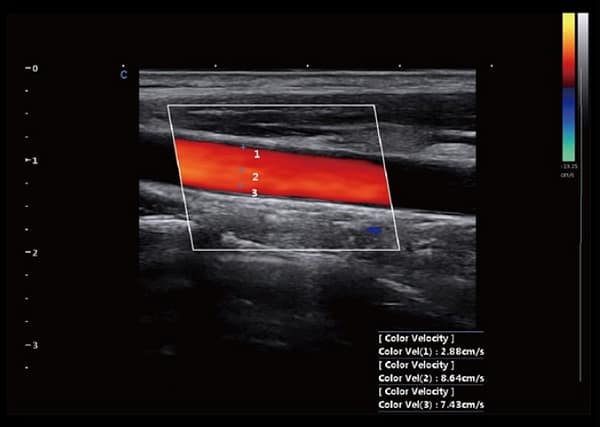

- Hình Ảnh Toàn Cảnh Màu: Phóng to vùng quét và cung cấp nhiều thông tin về màu sắc, đặc biệt hữu ích cho việc phân tích mạch máu lớn.

- SonoColor và SonoContrast: Cung cấp phân tích dòng định lượng và độ nhạy cao hơn, thích ứng với mọi loại đầu dò.